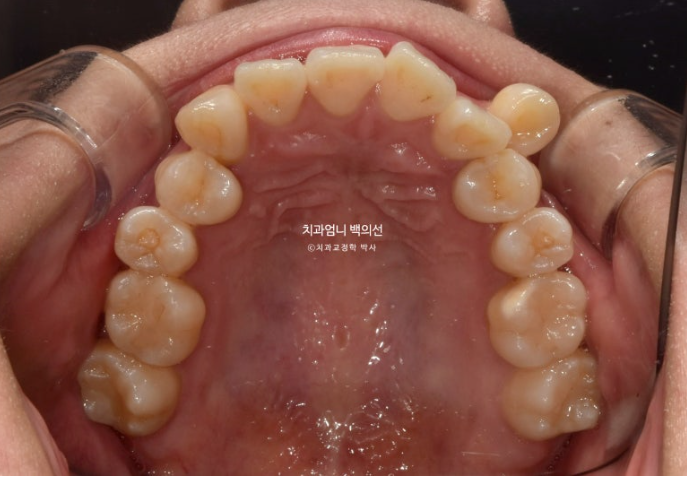

23.09

송곳니가 덧니가 제자리로 들어올 공간이 단 1mm도 없습니다.

심한 덧니입니다.

인비절라인으로 치료 원하셨고 비발치 치료를 원했기때문에 그에 맞게 치료계획을 세웠습니다.

아래는 사랑니가 있던 공간으로 어금니를 뒤로 밀어내어 최종적으로 아래 앞니가 뒤로 2mm 들어가도록 했습니다.

위도 마찬가지로 사랑니 공간으로 어금니들을 전부 후방이동 시켜 덧니가 배열될 공간을 얻기로 했죠.

덧니가 배열되면서 자칫 주변치아들이 처음보다 뻗쳐나오지 않도록, 치료계획이 조금 복잡하더라도 신경을 많이 써야 합니다.